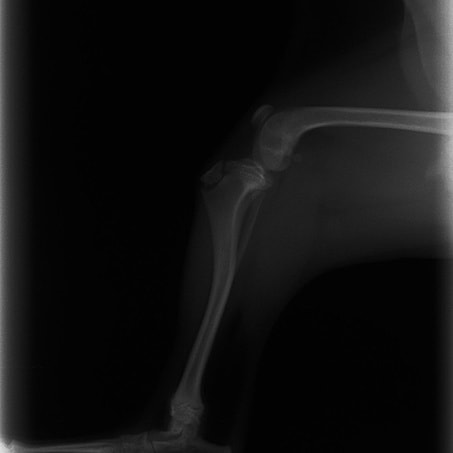

ペルシャ猫 11ヶ月齢 雄

他院にて左大腿骨遠位の成長板骨折(salter-harrisⅠ型)が認められており、治療相談を目的として来院。当院にて、キルシュナーワイヤーを用いたピンニングにより骨折部位の整復を行いました。術後の経過は良好で、現在も経過観察中です。

術前レントゲン